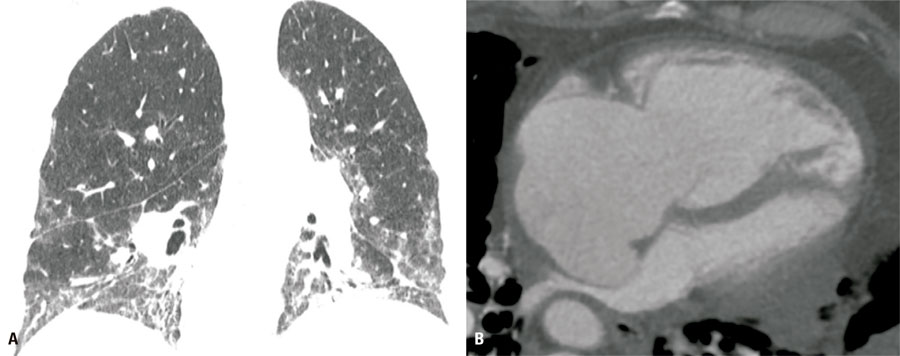

Computed tomography imaging features of major pulmonary and extrapulmonary complications of fibrotic lung diseases

Patients diagnosed with fibrosing interstitial lung disease are at risk of several complications, some of which may be life-threatening. Computed tomography imaging plays an important role in diagnosing these overlapping conditions. This article summarizes the computed tomography imaging features of the most common conditions associated with fibrosing interstitial lung diseases, categorized by involvement of the lung parenchyma or extra-pulmonary compartments. Some steps may help to recognize such complications, such as having knowledge of the underlying fibrotic lung disease, being aware of potentially immunosuppressive treatments in use, noting new relevant symptoms, checking previous imaging examinations to detect subtle changes, and considering the exam technique, for example, to avoid false perception of ground-glass opacities in exams with insufficient inspiration. Unenhanced computed tomography may be enough to diagnose most situations, but in specific cases, for example, in the clinical suspicion of pulmonary embolism, dedicated computed tomography angiography may be warranted. Careful comparison with previous exams is advised, especially to detect subtle opacities suspicious for lung cancer, underscoring that its detection may be difficult owing to the baseline morphological lung changes. Radiologists must be aware of such possible complications to perform early diagnosis and ensure proper management.